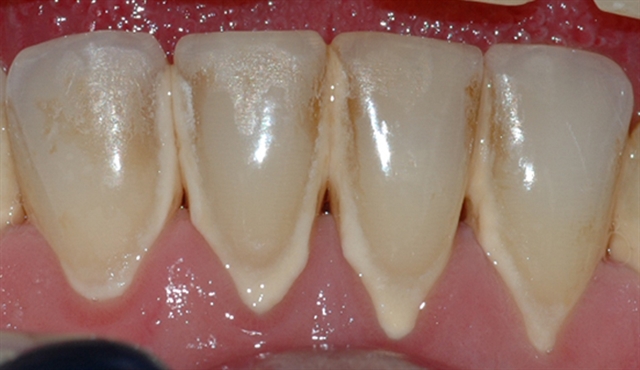

Bildet viser et nærbilde av tennene i underkjeven med tannsten og misfarging.

Bildet viser forholdene i underkjeven etter at tannsten og misfarging er fjernet